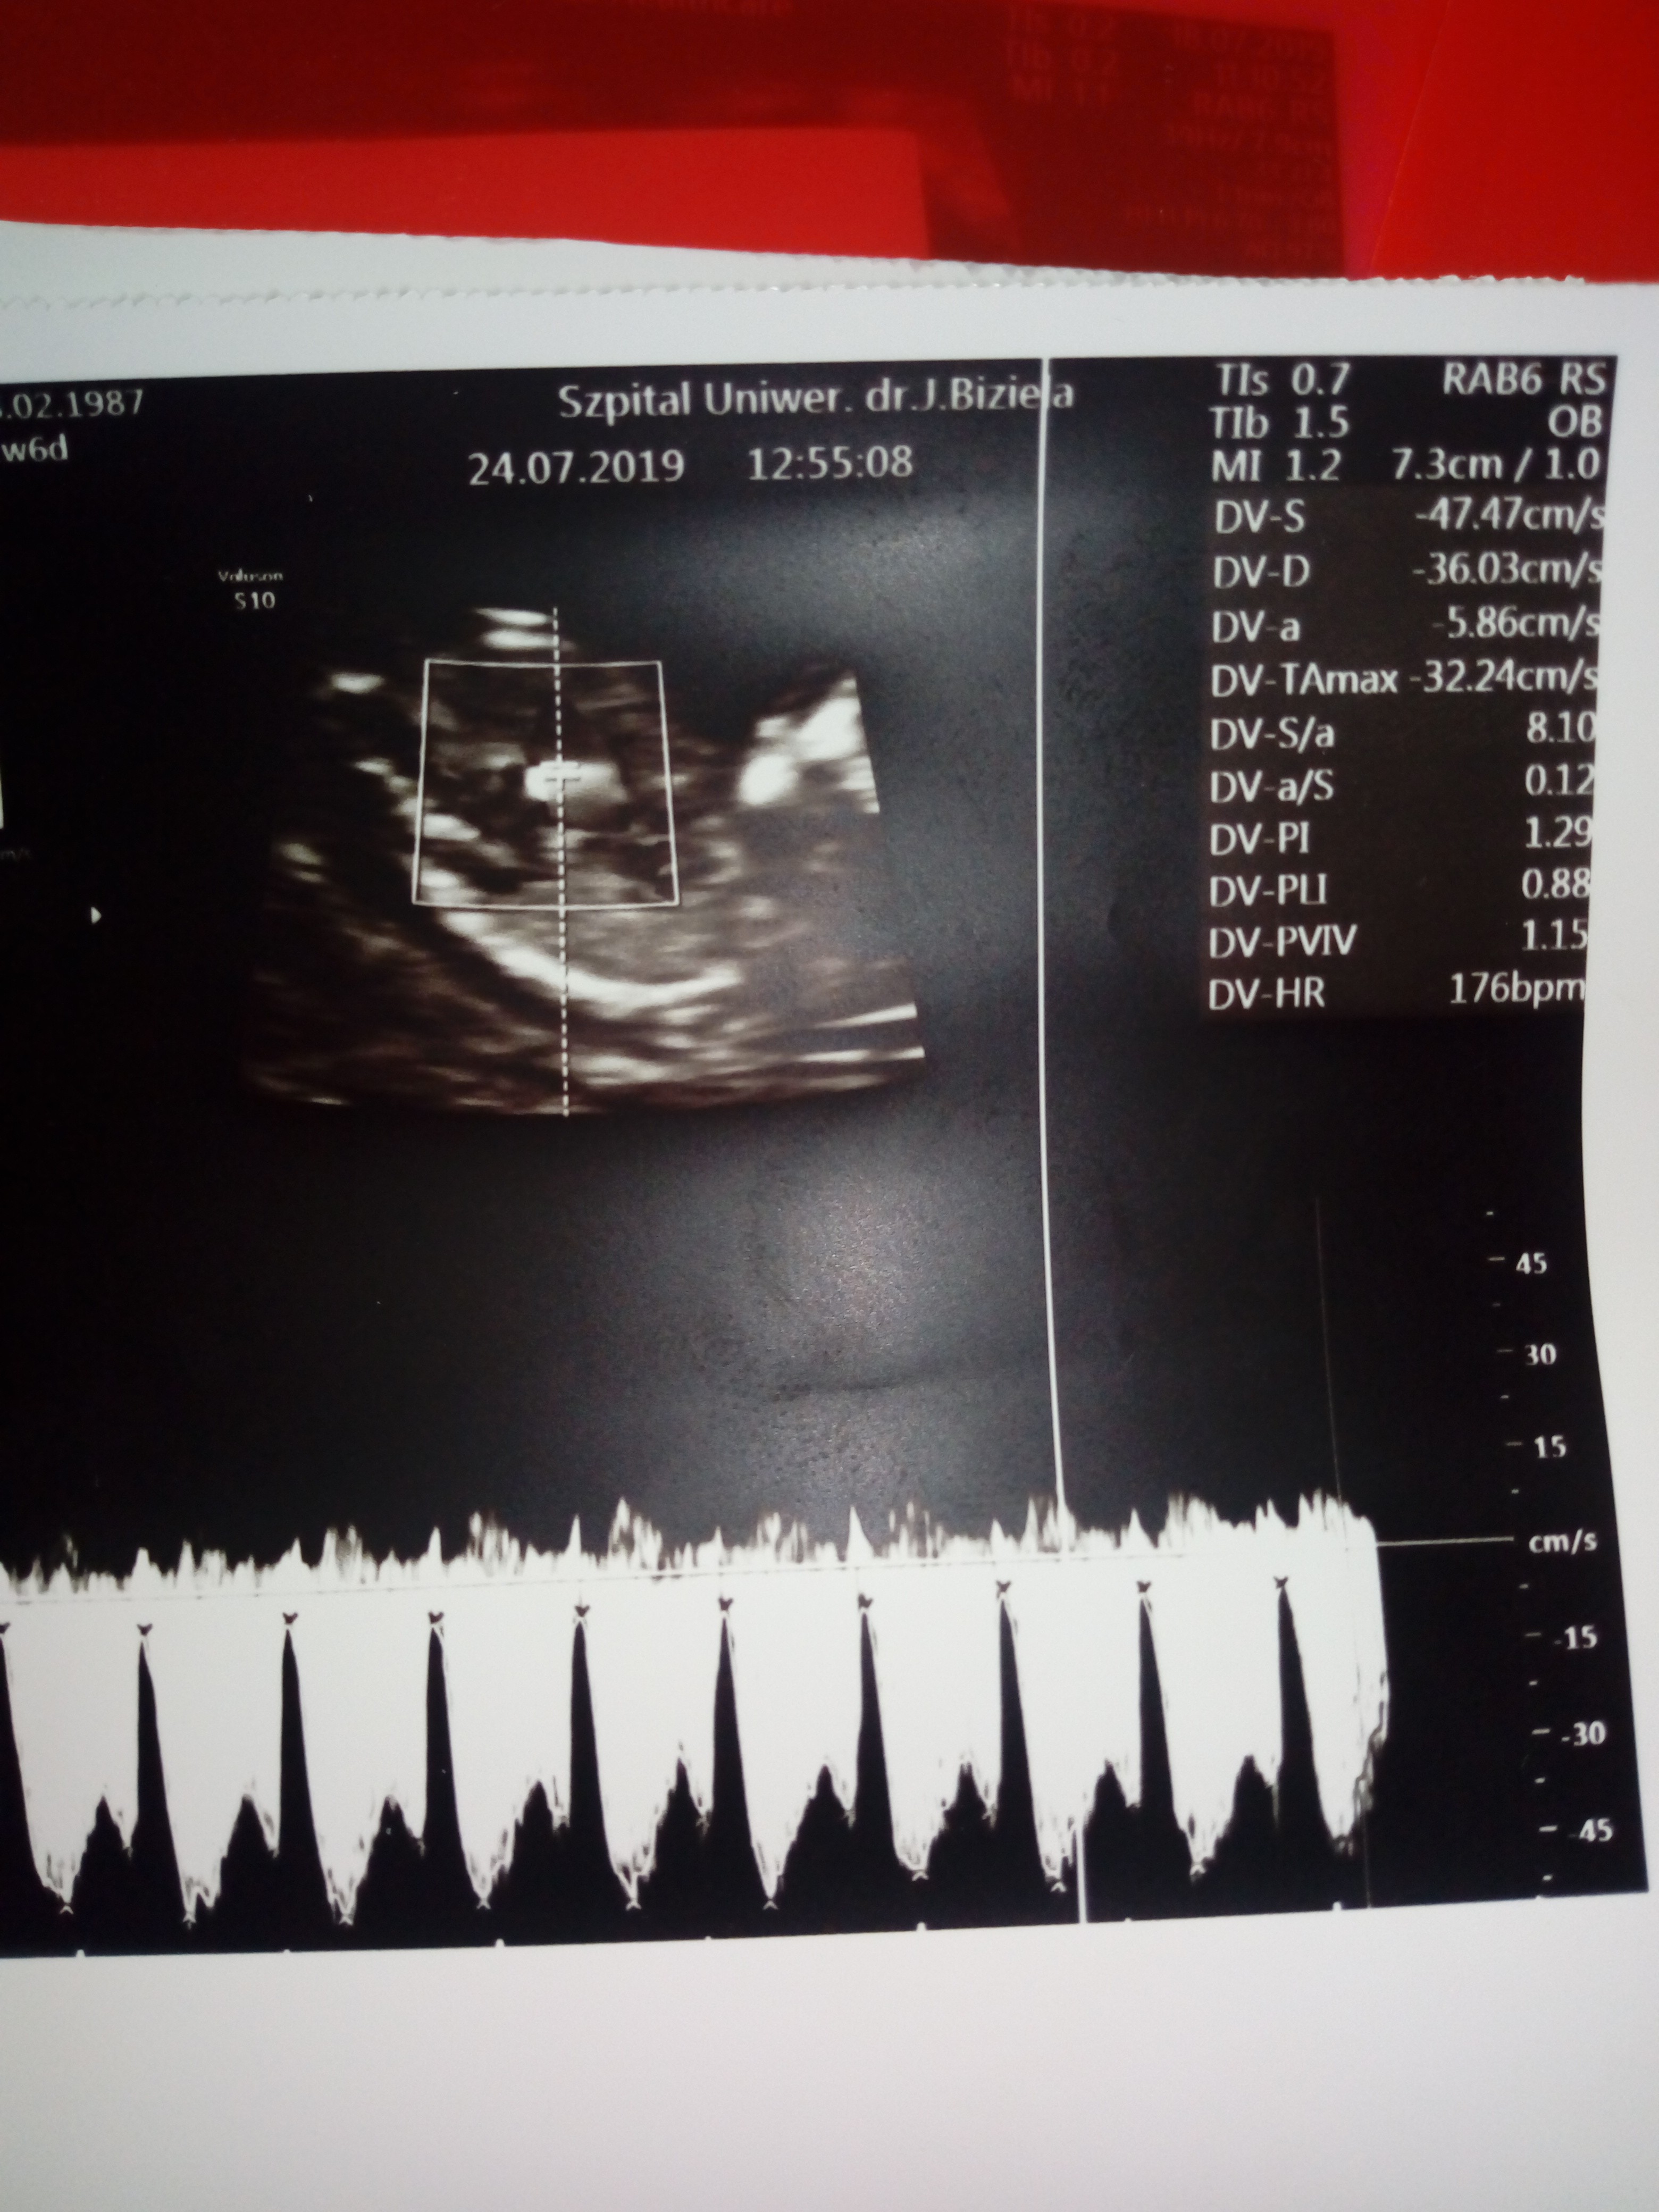

Cześć, znalazlam to forum po przekopaniu chyba całego netu w poszukiwaniu pomocy,rady,wsparcia?mam 32 lata,to moja 3 ciąża, z czego tylko jeden 7 mio latek w pelni zdrowy w domu, druga utracona w 7tc...Moj gin na rutynowej wizycie w 10 tc przyuwazyl NT rzędu 5,15 Kazal przyjechać po tygodniu gdzie NT wynioslo juz 2,4 Jednak mimo tego i jego zdaniem dobrego usg gdzie widzial kość nosowa,serce,narzady,rece,nogi wyslal mnie na prenatalne do Bydgoszczy do Biziela. Tam pani dr robila usg przez brzuch, przez pochwe i znowu przez brzuch bo male sie wiercilo Pomiary Nt wychodziły od 2,5 do 2,8 i tak w końcu wpisala Do tego obrzęk w okolicy karku plodu, Dv serca 1,29 Z uwagi na to WsZystko zalecila amnio ktore mam miec w dniu odbioru testu pappa po konsultacji z genetykiem....Boje sie tego badania poniewaz mam jelito drażliwe,od początku ciąży mam bóle brzuchu,zaparcia,skręty jelit...Mój gin mowi ze mogę zrobić test z krwi Nifty lub sanco Ale jeśli wyjdzie i tak wada to amnio mnie nie ominie jesli zdecyduje sie na terminacje ciąży...mam tydzień czasu na podjecie decyzji, przeczytałam większość wpisów tutaj Dziewczyny mowia ze badanie nic przyjemnego ale do przeżycia i u nich obylo sie bez powikłań...Doradzcie czy test z krwi Sanco czy amnio?

Usg prenatalne mialam juz we właściwym tyg czyli 11+6, Teoretycznie mam tylko opis badania usg ,ponieważ kolejka szla w,szpitalu w ten sposób ze najpierw mialam genetyka a potem po ok godzinie dopiero usg prenatalne wiec ryzyka oszacowanego typowo nie mam Zalaczam zdjecia dzidzi i opisu .Co do decyzji to została ona podjeta juz nawet przed ciążą,co by było gdyby....I moze zostanę zlinczowana przez kogos ale nie chodzi tu o mnie,o mój egoizm Myślę raczej całościowo Nie chce straszaka w przyszłości ewentualnie obarczac opieka nad chorym rodzeństwem...Poprostu nie...

W środę mam najpierw wyniki pappa, rozmowę z genetykiem i później ewentualnie amnio...Ja wiem ze nikt nie moze podejmowac decyzji za mnie Jestem tego świadoma